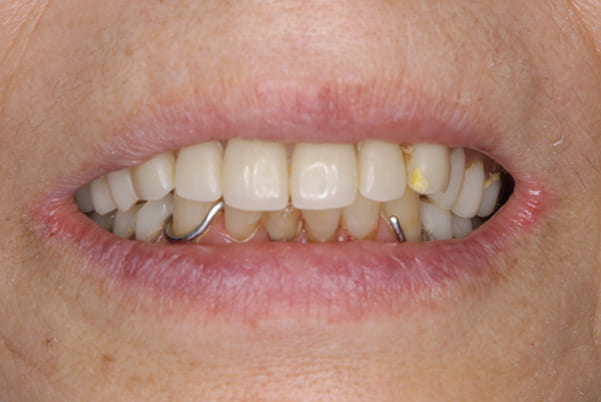

治療用入れ歯は患者様とご相談し、早急にお痛みをとり、お食事ができることをご希望されていたため、歯を抜くと同時に仮の入れ歯が入りお食事をされた後のお写真です。直ちに、お痛みを取り除き、お食事ができるような治療計画としました。

精密義歯は、歯をぬいたあと歯肉が治ってから、精密な入れ歯を作製しました。治療中も、仮の入れ歯があるため、普段の生活に支障がなく、また仮の入れ歯を実際使ってのご意見、ご希望(バネが気になる)をお聞きした上で、精密な義歯に、ご希望を反映し作製しました。

お写真は治療用の仮の入れですが普段通りお食事ができるとのことで少し食べ物もついています。。。